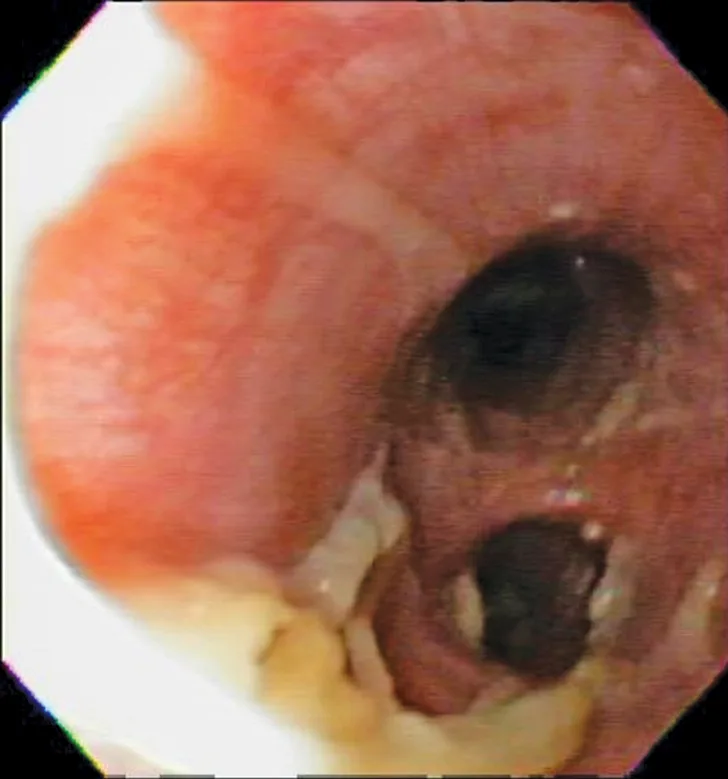

Characteristic cytologic eosinophilic inflammation. Pink granules typical of eosinophils can be seen (arrows).

Cytologic evaluation revealed a marked eosinophilic inflammatory response with no evidence of bacteria or sepsis; eosinophils made up 96% of total nucleated cells. The remaining cells were consistent with nondegenerate neutrophils (2%) and alveolar macrophages (2%) (Figure 3).

Cytologic evaluation of the airways confirms eosinophilic inflammation, which is the hallmark of diagnosis. The percentage of eosinophils (mean, 61% of the total nucleated cell population4) exceeds that of healthy dogs (5%-24%).2,5,10 Samples can be obtained via tracheal wash or bronchoscopy. Bronchoscopy allows for visualization of more characteristic airway associated changes (eg, greenish-yellow secretions, irregular mucosa, hyperemia).2,5,11 Occasionally, intraluminal granulomas may be present,4 allowing for mucosal brush samples or biopsies that can further support a diagnosis. Tracheal washes provide appropriate cytologic samples in most cases. Bronchoscopy is generally reserved for patients with more focal radiographic disease, concerns for neoplasia, or suspicion for concurrent structural disorders (eg, bronchial collapse, tracheal collapse).